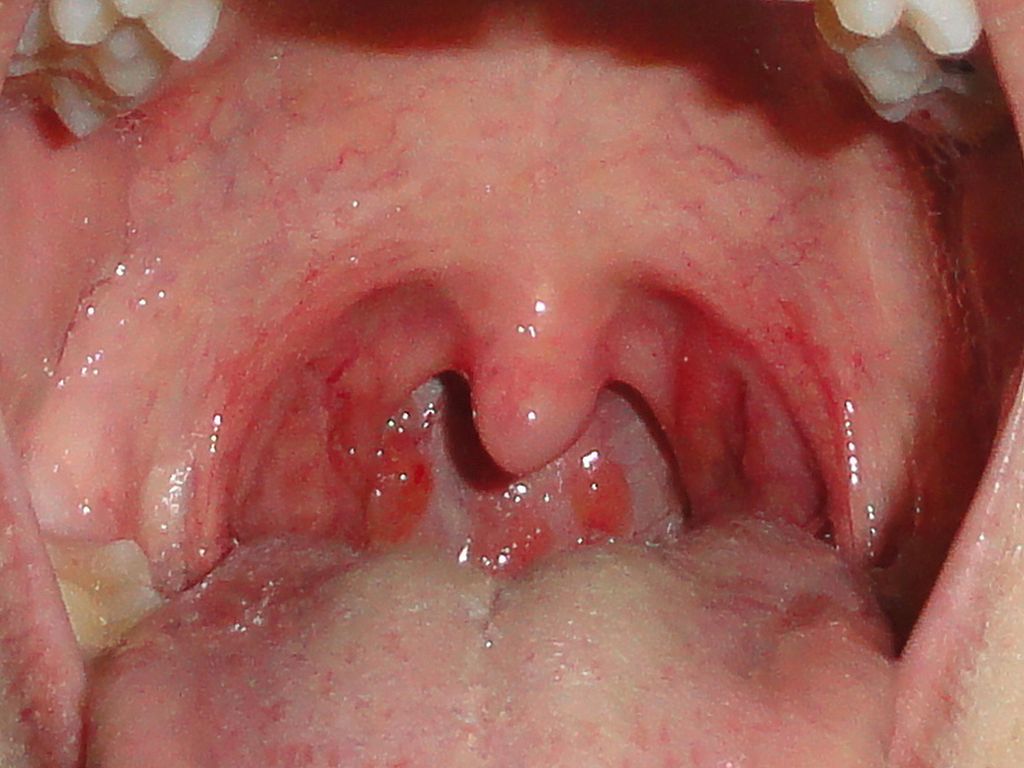

1. Masculino de 20 años de edad aparente a la cranologica, en malas condiciones generales, consiente, ubicado en tiempo, lugar y persona.Cavidad oral y faringe: eritema del paladar blando, úvula y faringe posterior. Torax y mov. De amplexión y amplexación simétricos. Murmullo vesicular, presente. Adecuada transmición de la voz. Claro pulmonar a la percusión, no se integra Sx Pleuropulmonar, ruidos cardiacos rítmicos de buen tono con adecuada intensidad y frecuencia.

1. DIAGNÓSTICO PRESUNTIVO: Faringoamigdalitis Estreptocócica

1. POR STREPTOCOCUS PYOGENES